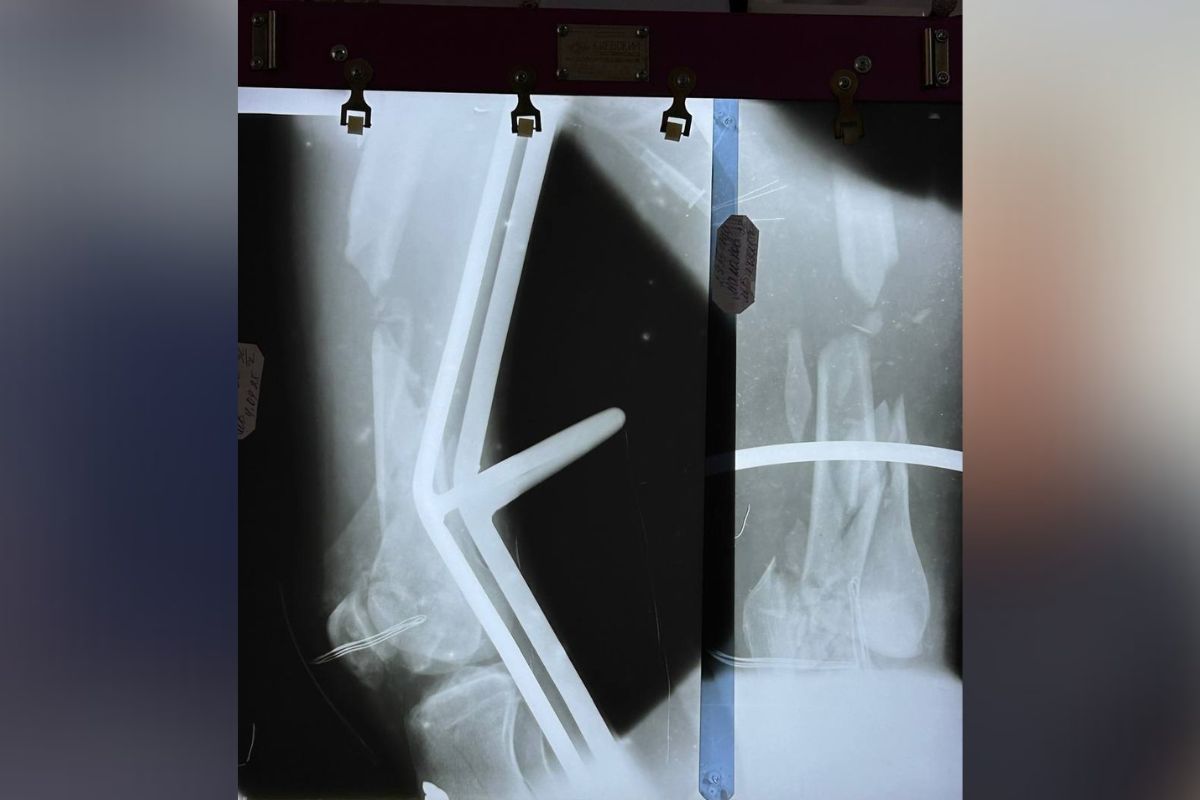

Унаслідок тієї ДТП Максим отримав важкі травми. Спершу допомагали друзі та рідні, і сім’я змогла оплатити дві операції. Чоловік потребує оперативного втручання на стегні, коліні та тазу.

На жаль, родина не може своїми силами покрити коштовне лікування вартістю 80 тисяч гривень. І тому просить допомоги у всіх небайдужих.